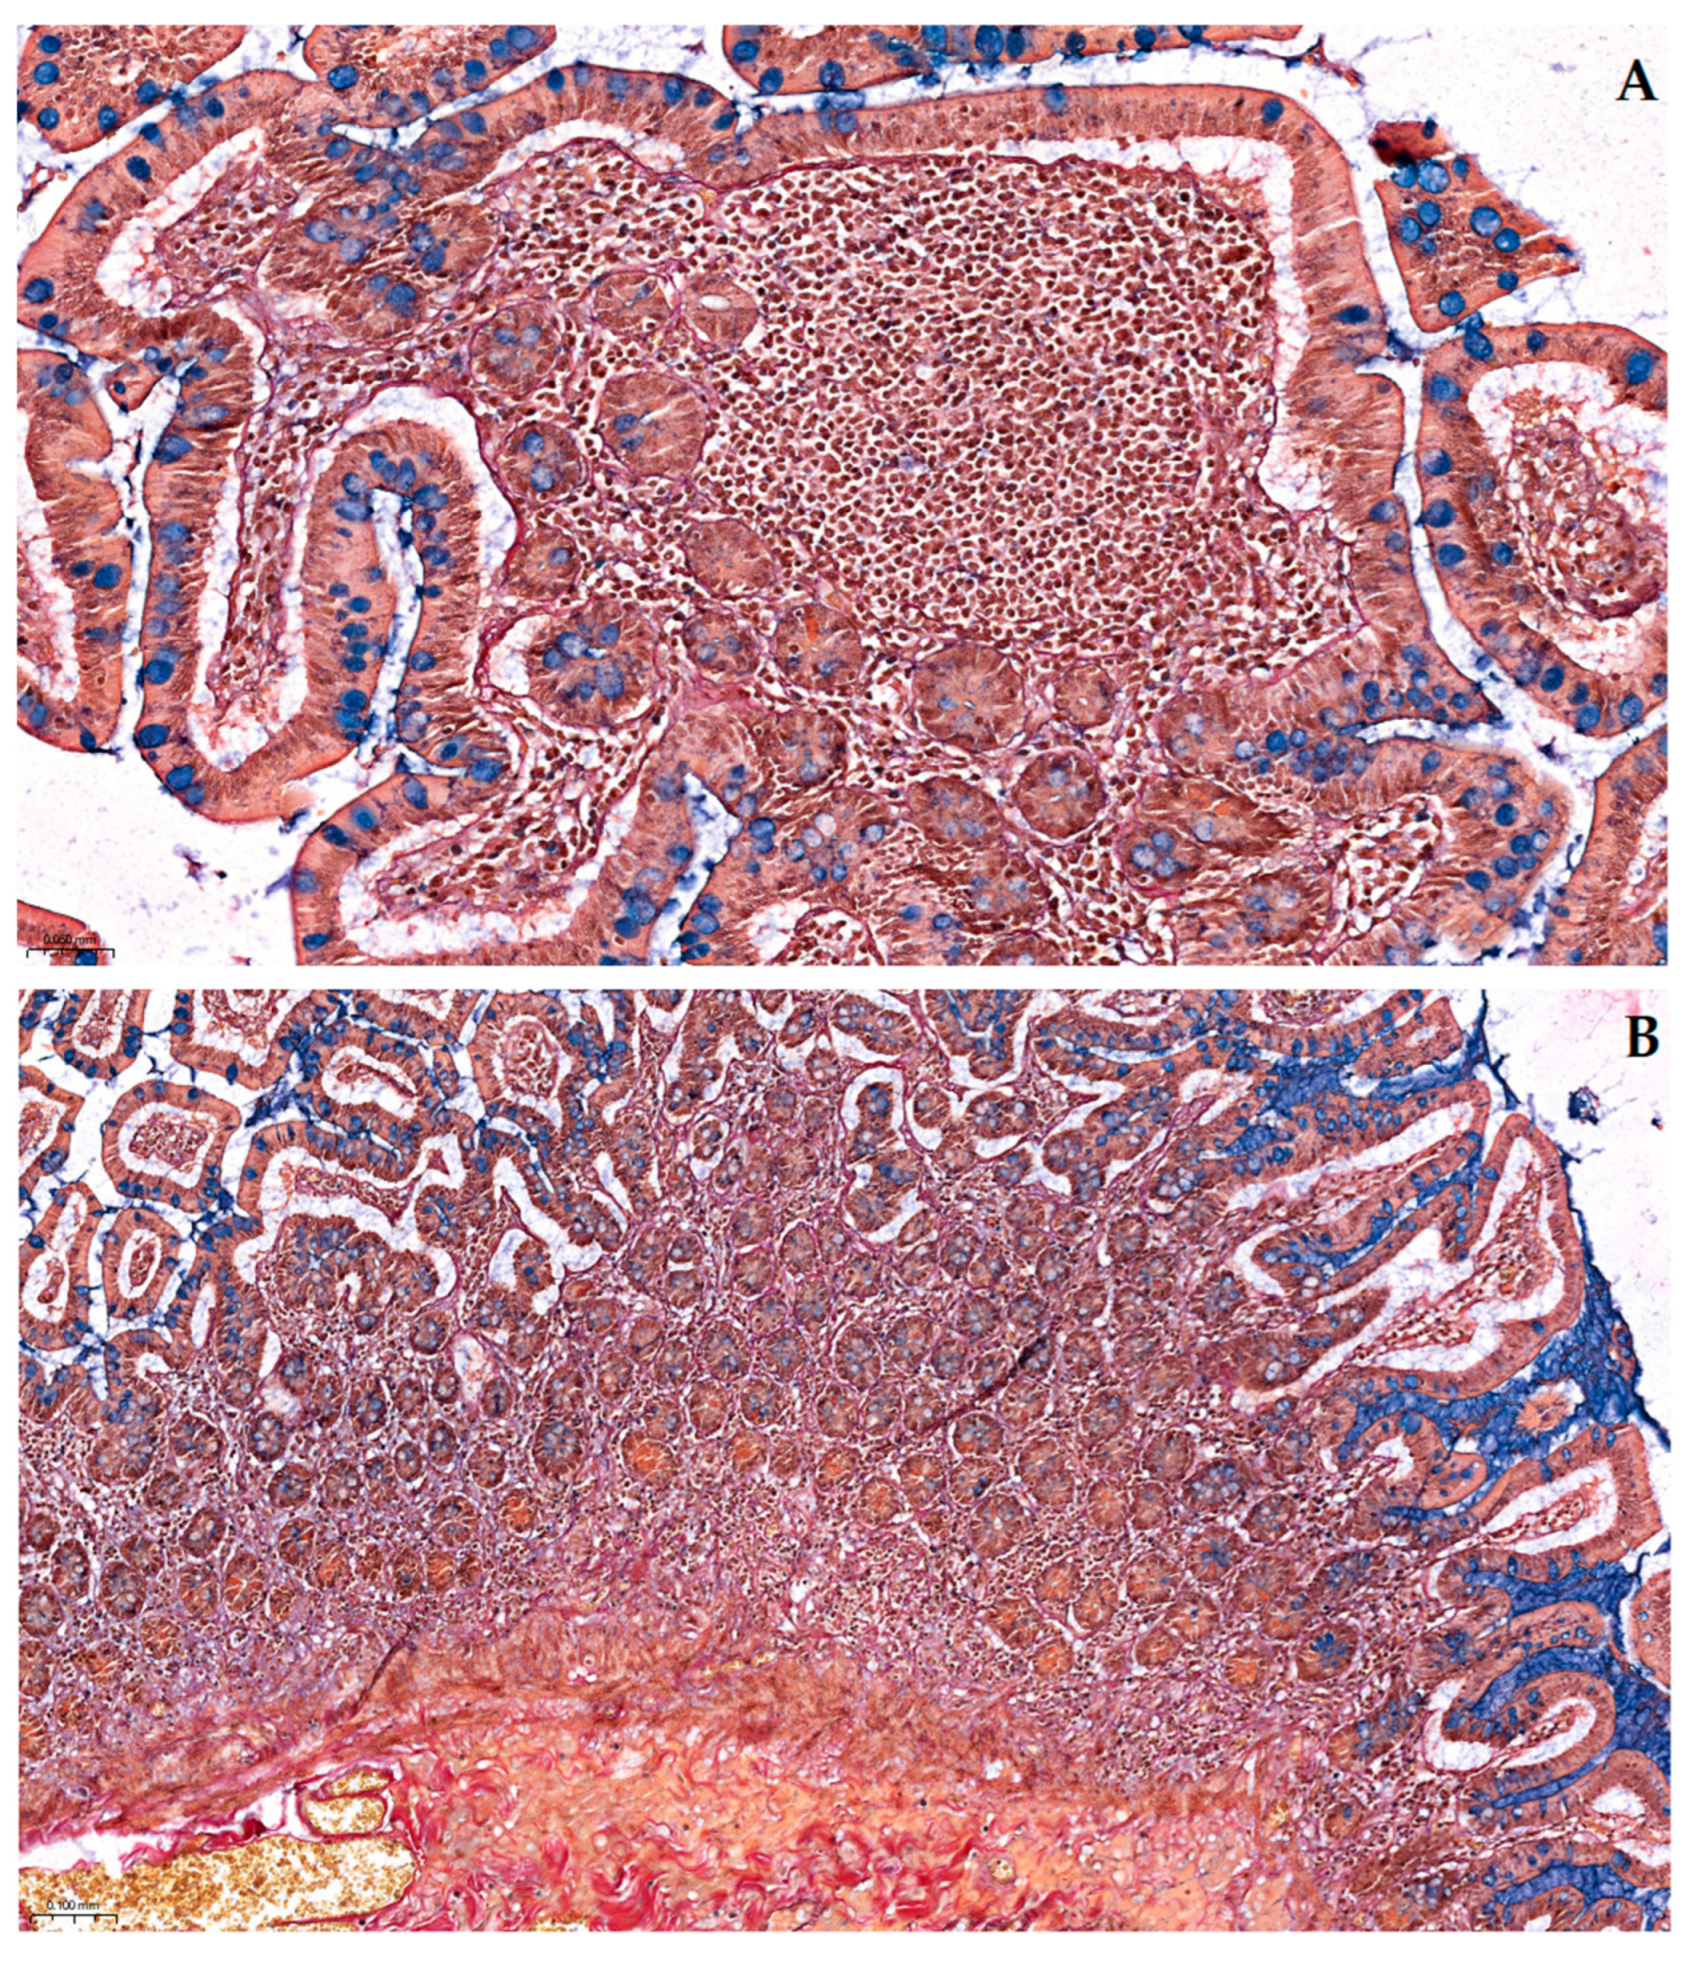

Pentachroma O-H produced vivid multicolor differentiation of all the targeted ileum tissue structures, clearly visualizing epithelial, stromal, lymphoid, and vascular components concomitantly, within the same section (see Figure 1 and Figure 2).

2.2.1. Comparative Sections Through Ileum Villi

At a high magnification (400×), in a longitudinal section through the intestinal villus (see Figure 1A and Figure 2), at the level of the ileum mucosa, the absorptive enterocytes lining the villus display, at times, crisp blue–black basal nuclei due to Mayer’s hematoxylin, whereas the abundant goblet cells are readily identified by their turquoise–blue apical mucin granules (Alcian Blue solution, pH 2.5). These stained goblet cell mucins stand out against the neighboring enterocytes, indicating acidic mucosubstances that would be nearly invisible in H&E, due to wash-out during processing. Beneath the mucosa, a well-highlighted basement membrane is clearly discernable, creating a diffusion interface between the overlaying epithelium and the subjacent loose connective tissue (see Figure 1A).

Conversely, Figure 1B, a transverse section through adjacent villi, highlights the circumferential arrangement of the epithelial layer encircling each villus. Central goblet cells filled with blue alcianophilic mucin punctuate the epithelial rosettes, while the surrounding lamina propria also shows, as described above for the longitudinal section, the full array of Pentachroma O-H-specific connective tissue interactions: scarce red collagen fibers in the villus core (acid fuchsin); distinct golden–yellow vascular smooth muscle and yellow-to-orange erythrocyte cytoplasmic elements (picric acid); and thin stromal black–purple strands of elastin (resorcin–fuchsin).

Figure 1. Pentachroma O-H staining of human ileum mucosa at high magnification (400×)—Comparative sections: (A) longitudinal section through an intestinal villus showing surface epithelium composed of absorptive enterocytes with basal blue–black nuclei (Mayer’s hematoxylin) and scattered goblet cells, whose acidic mucins are highlighted in turquoise–blue (Alcian Blue pH 2.5). The lamina propria core contains capillaries, connective tissue, and scattered elastic fibers; (B) transverse section through adjacent villi at the same magnification, revealing the circular arrangement of epithelial cells, with centrally located goblet cells, rich in acidic mucins (turquoise–blue), and a surrounding stroma, composed of red-stained collagen (Van Gieson’s acid fuchsin), yellow-to-orange cytoplasmic (i.e., erythrocytes) and muscular elements (picric acid), and black–purple elastic fibers (Weigert’s resorcin–fuchsin) distributed within the lamina propria. Scale bar: (A)—0.010 mm; (B)—0.020 mm.